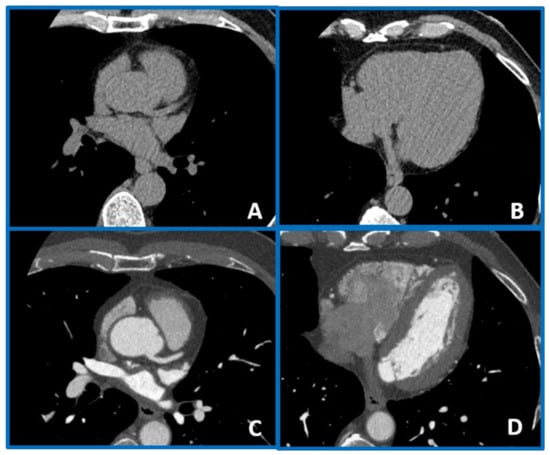

| Remodeling index (RI) | Ratio between lesion plaque area (red circle) and reference lumen area (blue circle). Positive remodeling is defined as RI > 1.1. | ![]() |

| Low-attenuation plaque (LAP) | Presence of any voxel < 30 HU in a coronary plaque. | ![]() |

| Plaque burden (PB) | Derived by the following formula: (lesion plaque area (red circle)—lesion lumen area (blue circle))/lesion plaque area (red circle). | ![]() |

| Napkin-ring sign (NRS) | Presence of rim-like thin enhancement (no more than 130 HU) distributed along the outer contour of the vessel and surrounding a fibro-lipidic plaque. | ![]() |

| Small spotty calcifications (SC) | Any discrete calcification ≤ 3 mm in length and occupying ≤ 90° arc when viewed on short axis. | ![]() |